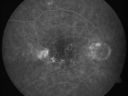

PED - Exudate (fellow eye RPE Hyperplasia)

FLUORESCEIN ANGIOGRAM: Shows an occult subfoveal choroidal neovascular membrane in the left eye about 4 disc areas in size. The right eye has staining of drusen and hypofluorescence corresponding to the macular pigment. Temporal to the fovea, about 1-disc diameter from the center, there is a disc area of irregular hyperfluorescence. It is associated with a spot of hemorrhage, which may represent an occult asymptomatic extrafoveal choroidal neovascular membrane.